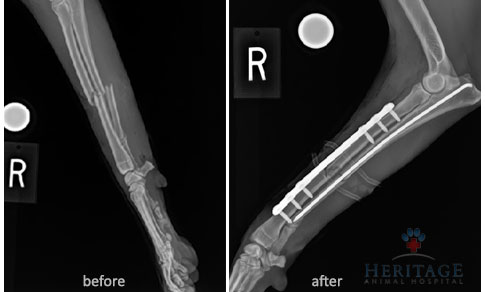

- Fractures — when hit by a car or other accidents